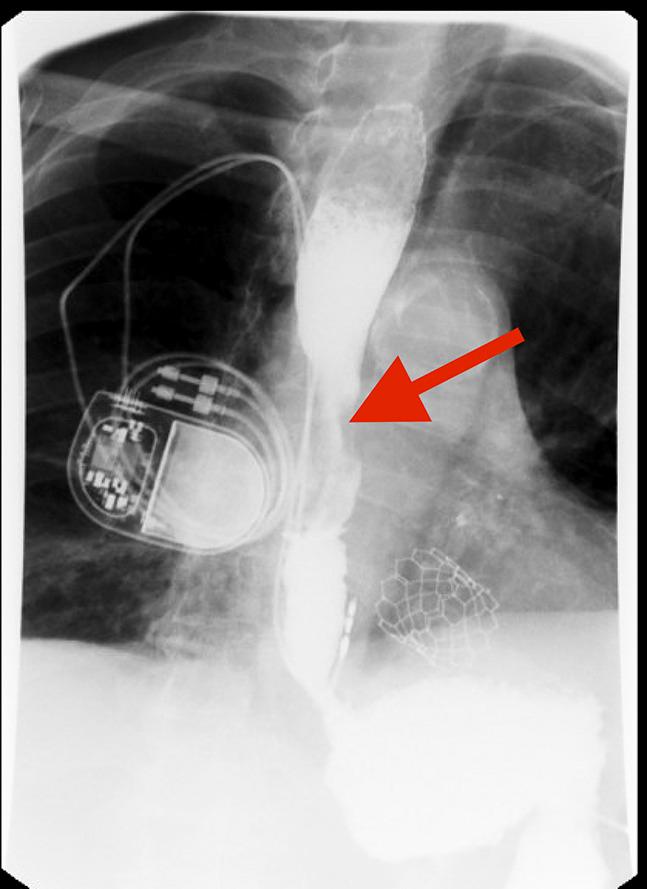

Swallowed by the Past: Dysphagia as a Decade-Late Manifestation of Renal Cell Carcinoma Recurrence.

https://cdn.ncbi.nlm.nih.gov/pmc/blobs/2783/12055172/c5cebae68321/ac9-12-e01693-g001.jpg